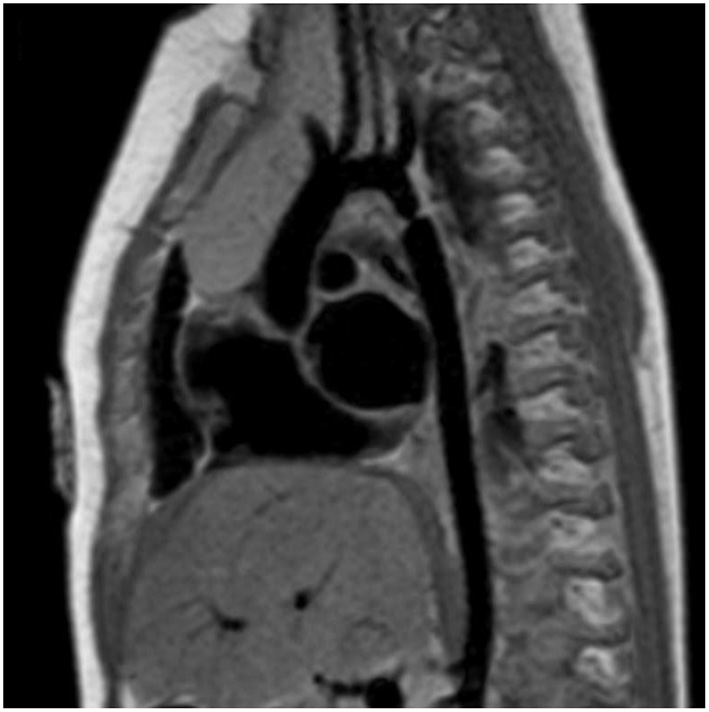

MRI and CTA complement echo with more complete 3D visualization of the thoracic aorta (Figure 2). A comparison of the strengths and weaknesses of echocardiography, MRI, and CTA are outlined in Table 1 (59–61). MRI flow analysis findings indicating increasing isolated CoA severity include decreased acceleration rate and peak and time averaged flow, delayed onset of descending aorta flow compared to the ascending aorta, prolonged deceleration with increased antegrade diastolic flow and increased descending aorta collateral flow (62). Advances in MRI 3D flow analysis (4-dimensional flow) correlate with invasively measured pressure gradients (63) (Figure 3). Future work in MRI 4D flow and computational fluid dynamics may identify patients at higher risk for developing re-coarctation and/or aneurysms (64, 65).

Figure 2

Cardiac magnetic resonance imaging (MRI) of isolated CoA. Cardiac MRI showing a discrete and isolated CoA. This modality offers high resolution imaging of the entire aortic arch, helping localize the extent and significance of the coarctation.